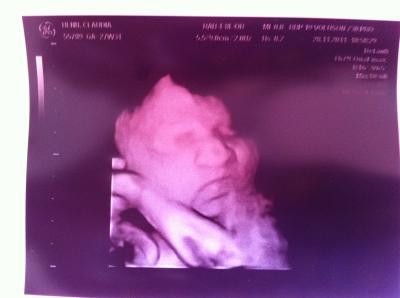

Hallo ihr lieben, endlich konte ich gestern meine kleine Nudel auch mal in 3D betrachten :), nur leider hat sie ihre Nase gegen mein Mutterkuchen gedrückt, so das wir erstmal Schwierigkeiten hatten ein schönes Foto von ihr zu bekommen. Dafür habe ich jetzt ganz viele süße Fotos von meiner kleinen mit plattgedrückter Nase Ansonsten ist alles super, ihr gehts gut und wiegt jetzt 1098g bei ca. 35cm

Bild zu Endlich auch 3D - Forum für Februar - Mamis